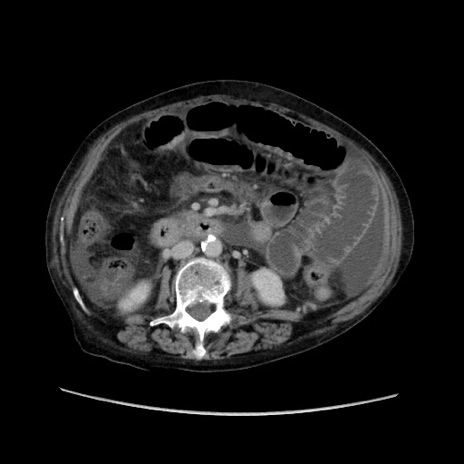

症例31(横断像)

【症例】80歳代 女性

【主訴】腹部膨満感

【現病歴】他院にて肝硬変にてフォロー中。1週間前から便秘、腹部膨満感、臍部腫瘤あり受診となる。

【既往歴】肝硬変

【身体所見】腹部膨隆あり、皮膚変化なし、疼痛なし。

【データ】WBC 4600、CRP 0.25